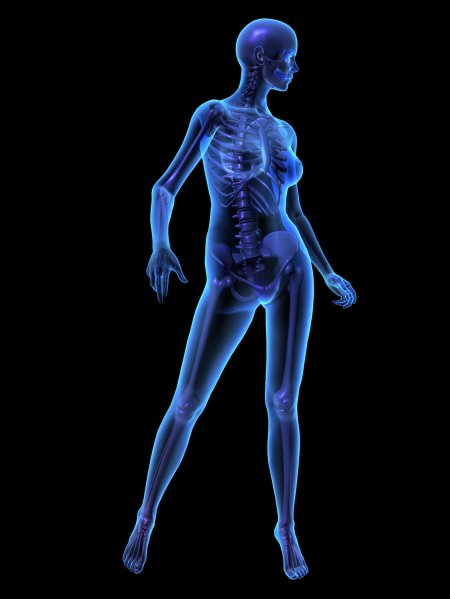

Рентгеновский эффект создает фантастические композиции в этих фотографиях девушки, чье тело становится прозрачным, демонстрируя скелет и внутренние органы. Она позирует в разных позах, ее силуэт светится загадочным свечением. Каждый кадр передает атмосферу научной фантастики и медицинского искусства. Ее кожа кажется полупрозрачной, позволяя увидеть кости и мышцы. Фотографии рассказывают о хрупкости человеческого тела и его внутренней красоте. Девушка то стоит в задумчивости, то делает грациозное движение. Эти иллюстрации вдохновляют на размышления о человеческой анатомии и уязвимости. Каждая картинка - это момент прозрения, когда внешнее уступает место внутреннему. Девушка воплощает образ современной Медузы, сочетающей красоту и загадочность.

Сквозь материю: тайны анатомии